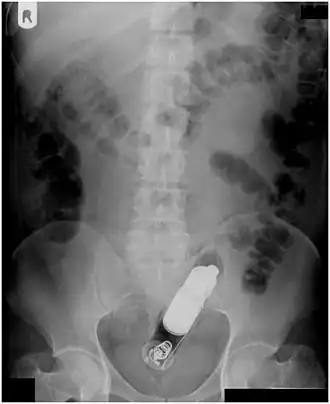

| A foreign body - in this case a swallowed toothbrush - located in the stomach cavity by using an endoscope. | |

Abdominal X-ray showing small packages of cocaine swallowed by a trafficker. -